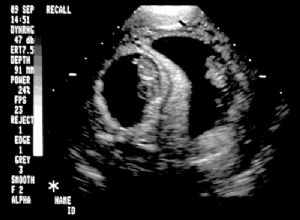

Normal twin intrauterine pregnancy.